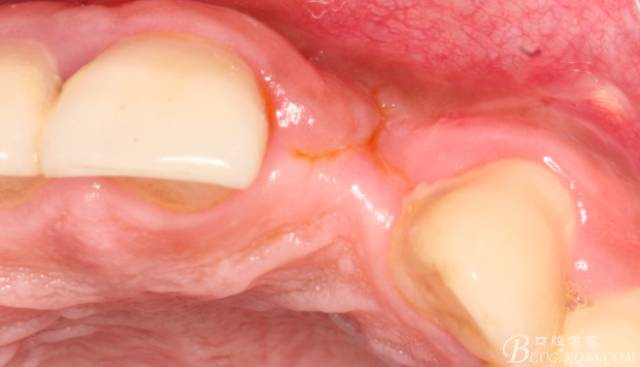

4個月后,唇側(cè)豐滿度尚可,與鄰牙之間齦乳頭完整。

保留齦乳頭翻小瓣。

翻開后驚喜的發(fā)現(xiàn),術(shù)區(qū)成骨非常好,去除部分骨才暴露那顆長鈦釘。